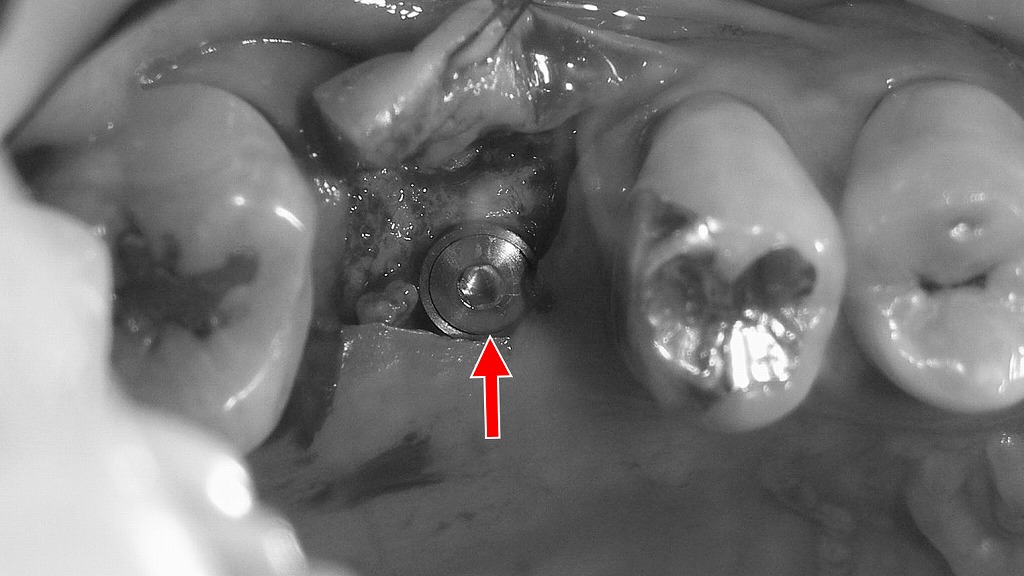

インプラント

上顎6番欠損に対するインプラント治療の術前・術中・術後の経過です。

欠損部の状態を正確に診断したうえで、骨の質や量を考慮しながらインプラントを適切な位置に埋入しました。

術後の被せ物を装着したレントゲンでは、インプラントが骨内に安定して固定されていることが確認でき、噛む機能と咬合の回復を図っていきます。